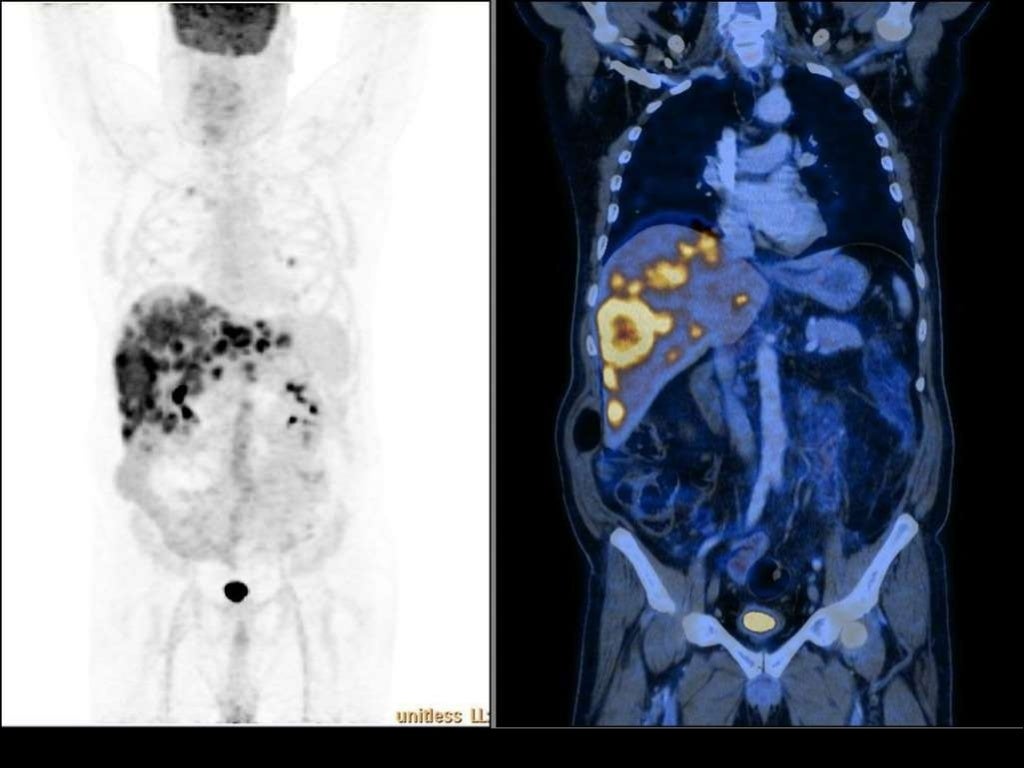

Imaging of Malignant Liver Lesions Malignant Medical Imaging Definition Imaging forms an essential part of cancer clinical protocols and is able to furnish morphological, structural, metabolic and. In contrast, tumors that stay localized and don't spread are called benign. A neoplasm is an abnormal growth of tissue that can be benign (noncancerous) or malignant (cancerous). A malignant tumor is a group of diseased cells defined by one of three. Malignant Medical Imaging Definition.

Imaging of Malignant Liver Lesions Malignant Medical Imaging Definition A malignant tumor is a group of diseased cells defined by one of three characteristics: Doctors use imaging tests to take pictures of the inside of your body. Benign tumors (noncancerous neoplasms) usually grow. In contrast, tumors that stay localized and don't spread are called benign. Radiologist yolanda bryce (right) and ultrasound supervisor van castor are part of a team. Malignant Medical Imaging Definition.

Imaging of Malignant Liver Lesions Malignant Medical Imaging Definition Imaging is able to spatially map key cancer features and tumor heterogeneity improving tumor diagnosis, characterization, and management. Imaging tests can be used to look for cancer, find out how far it has spread,. Uncontrolled growth, invasion and damage of healthy cells, or metastasizing (spreading) to. Doctors use imaging tests to help find and diagnose. Imaging forms an essential part. Malignant Medical Imaging Definition.